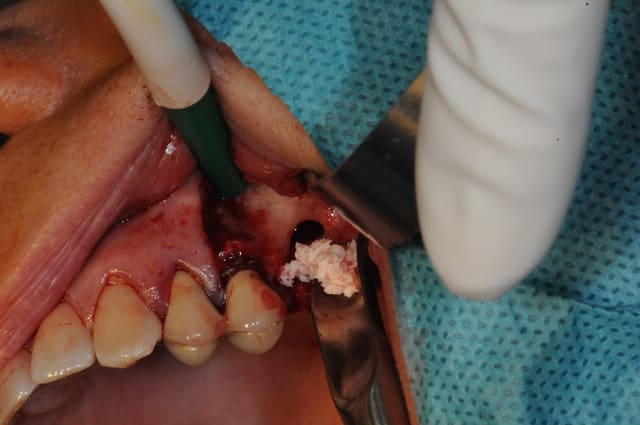

je fais bref!

déjà ne fais pas la même chose que moi; décales ton trait d'incision par rapport à l'entrée de la CBS

- coupes la communication entre la membrane de Schneider et la muqueuse (ici, c'était à moitié de la gencive et de la boule de Bichat mélangée avec du tissus de granulation)

- cautérise avec un bistouri électrique ou un simple bistouri chauffé à blanc.

- refoules le sinus

- prf

- combles (Rog +membrane, ...)

-sutures et le tour est joué.

fais nous des photos, les miennes sont pourries, les piles étaient nazes...

bonne chir, je t'envie.!!